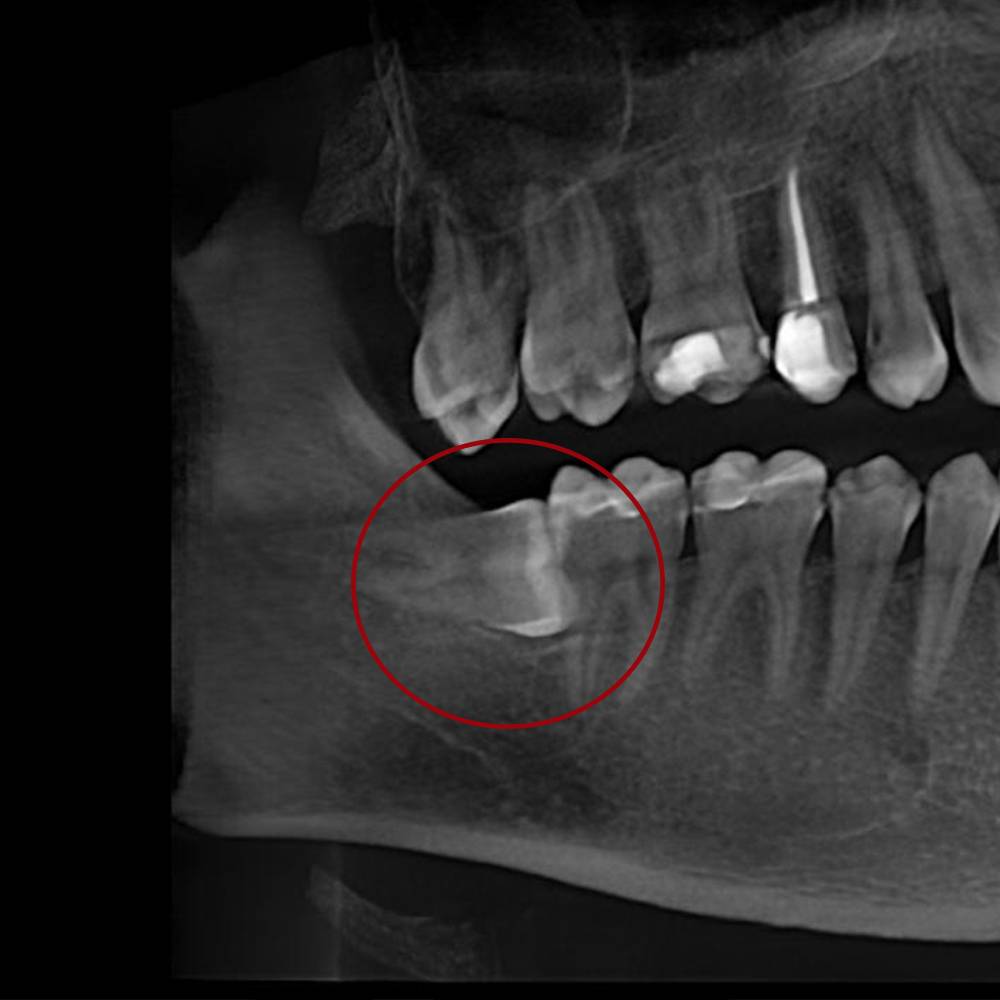

Головний різновид – складне видалення зуба мудрості. Ці маніпуляції проводяться тільки після комплексної діагностики та призначення стоматолога. Метод втручання залежить від розташування зуба мудрості, кількості коренів і типу патології. Видалення верхніх вісімок зазвичай проходить легше, зважаючи на меншу товщину кістки, якщо порівнювати з нижньої щелепою. Крім того, набагато частіше трапляється дистопія та ретенція саме нижніх зубів мудрості. Вони можуть бути частково чи повністю занурені в ясна, прорізуватися під кутом чи рости горизонтально в напрямку сусідніх молярів.

Як і складне видалення 8 зуба, складне видалення коренів зубів – втручання, яке не можна відкладати, щоб не погіршити стан порожнини рота та здоров’я загалом. Лікар призначає хірургічні маніпуляції в таких клінічних випадках, як:

- повне руйнування коронки зуба із сильними патологічними змінами коренів;

- патологічна рухливість зуба через запущений пародонтит;

- тріщина чи перелом кореня зуба.

Складне видалення зуба мудрості чи іншої одиниці призначається, коли діагностовано кісту чи гранульому, яку не можна прибрати без екстракції зуба. Ще один різновид – це маніпуляції з видалення одиниці із сильно зруйнованою коронкою, коли лікар спочатку виконує розпилювання зуба на частини, потім витягує кожну окремо та ретельно чистить лунку з подальшим накладанням швів на ясна.